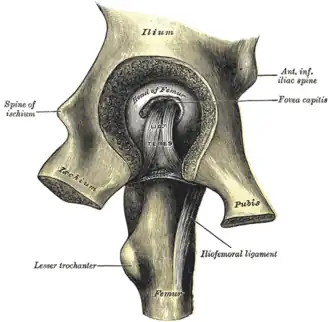

Left hip-joint, opened by removing the floor of the acetabulum from within the pelvis

Left hip-joint, opened by removing the floor of the acetabulum from within the pelvis -